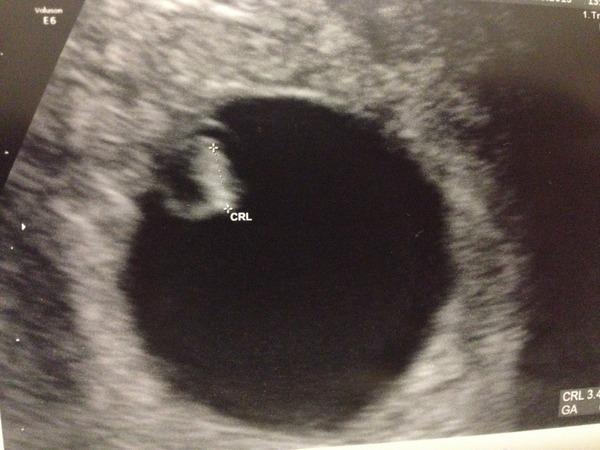

Sorry for self centred post ladies, but introducing Choccy Bean Grin

Strong HB, Dr really pleased and everything as it should be.

Can't believe it, still in shock I've got this far. Been a long 18 months!!

Aaaw, how lovely! Congrats choccy on your lovely little bean x

Aww that's brill Choccy! How did you manage to get a pic? I wasn't even allowed to take a picture of mine and my OH wasn't with me - I feel cheated out of being able to share with him :(

I just asked for one but they'd already printed it out when I was getting dressed.

congrats choccy looking fab! how far along are you?

Only 6 weeks Ginger so a loooooong way to go yet.